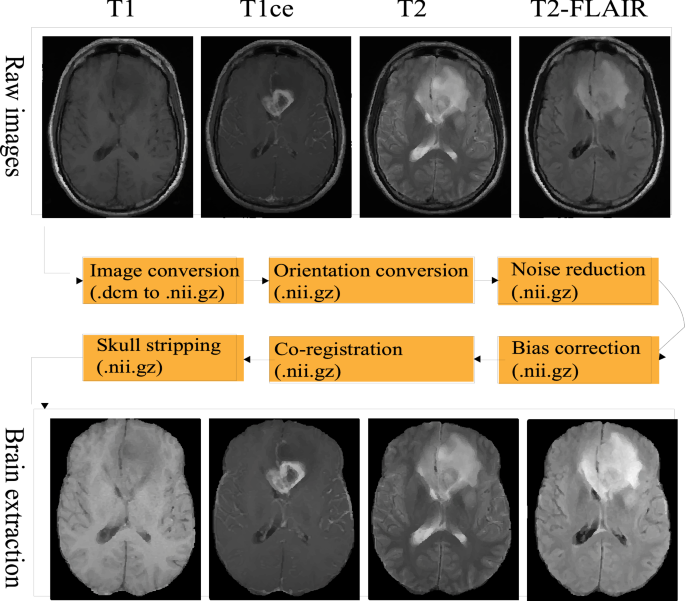

The whole workflow of brain extraction is shown in Fig. 1. Firstly, we convert the raw digital imaging and communication in medicine (.dicom) multiparametric images into a compressed neuroimaging informatics technology initiative (.nii.gz) format, then change the orientation same as to the SRI24 atlas41. There are then two optional pre-processing steps: noise reduction and bias field correction. Subsequentially, each imaging modality registers to the atlas (1 mm × 1 mm × 1 mm), so that all image modalities are aligned into the same space having resolution of 1 mm × 1 mm × 1 mm. Thereafter, all co-registered isotropic image modalities are stacked following the sequence of T2-FLAIR, T1, T1ce, and T2. Finally, the fused images (dimension: \(4\times 155\times 240\times 240\)) are fed into the proposed deep neural network model to obtain a binary mask for skull stripping. The co-registered brain extraction is accomplished by multiplying the binary mask to the co-registered images.